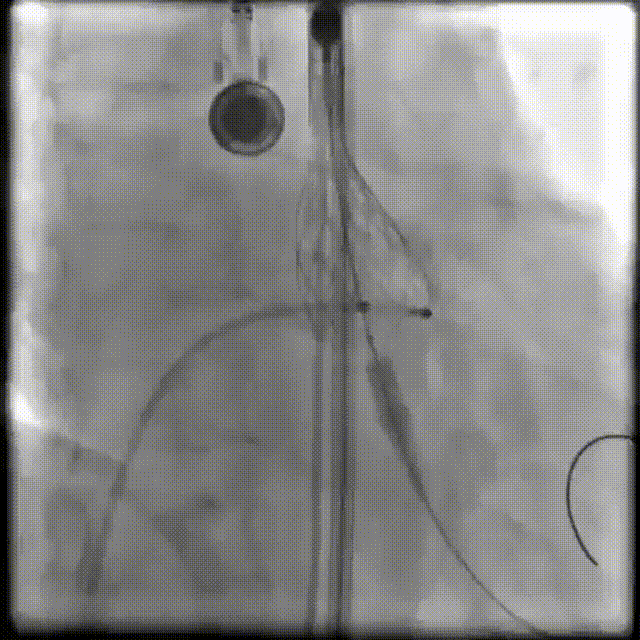

输送系统定位

瓣膜释放

珠海市人民医院超声科张恒教授术中使用食道超声评估瓣膜形态、瓣膜植入深度、反流及瓣周漏情况

术后超声:峰值流速1.06m/s,跨瓣压差6mmHg

瓣膜释放位置佳,释放后瓣膜工作正常,无明显瓣周漏及传导阻滞情况。患者的平均跨瓣压差由术前的50mmHg改善至术后的6mmHg, 主动脉瓣瓣口峰值流速由术前的5.1m/s改善至术后的1.06m/s,患者获益明显。